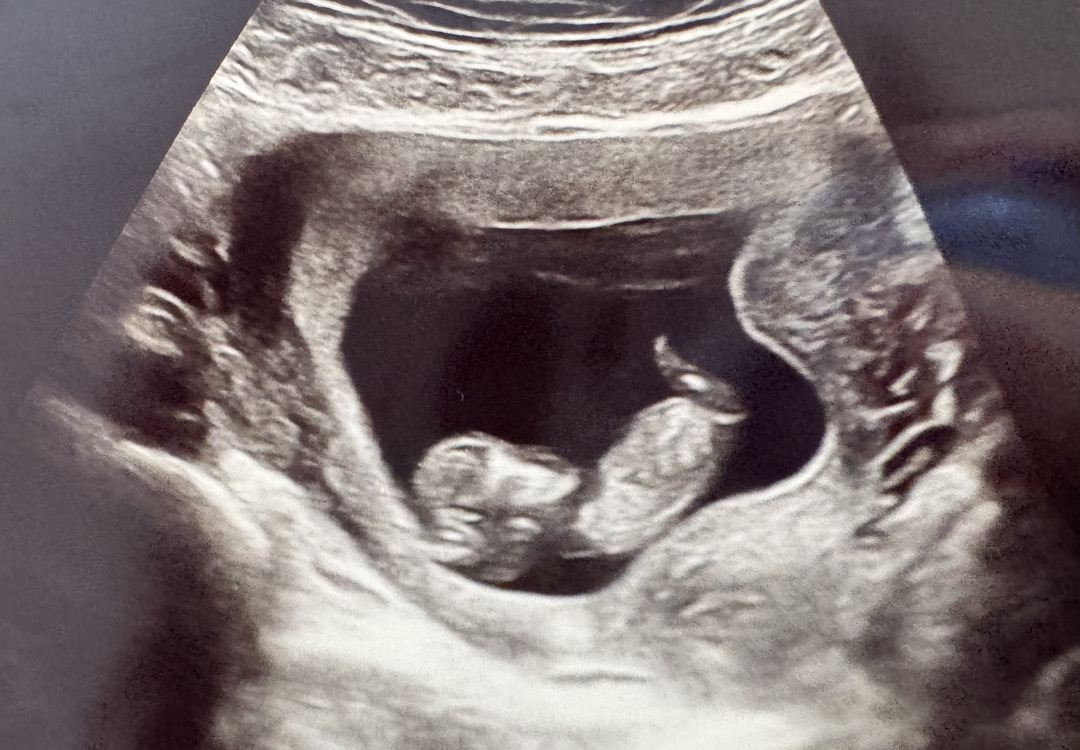

11주 5일 각도법 봐주세요!🙏🙏

혹시 알수있을까요오..? 미리감사드립니다🙏

이건 다른사진이에요!